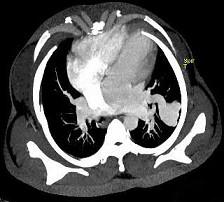

问题 男性,26岁,头晕、气逼三年余,CT检查如图所示,请选择的最可能诊断 ( )

选项 A、动静脉畸形 B、动脉瘤 C、毛细血管扩张症 D、毛细血管瘤 E、海绵状血管瘤

答案 A